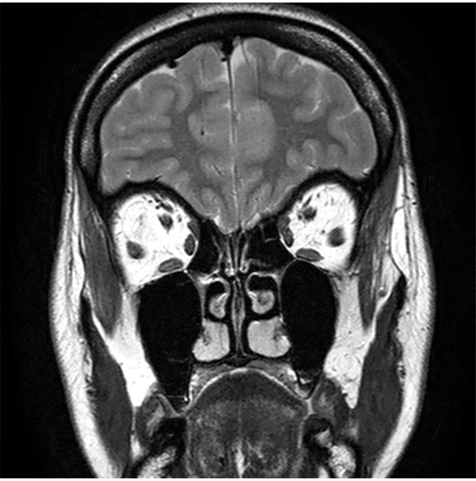

L’imagerie centrée sur la région orbitaire et péri-orbitaire incluant le scanner et l’imagerie par résonance magnétique (IRM) est devenue particulièrement indispensable. Pour les syndromes congénitaux, l’IRM effectue une analyse de l’oblique supérieur dans sa totalité (tendon, poulie et corps). Elle permet de mettre en évidence plusieurs types d’anomalies du muscle oblique supérieur à type d’hypertrophie du complexe poulie-tendon (fig. 14-23a), poulie-tendon-corps (fig. 14-23, b et c), de la poulie et d’anomalie du tendon (plus long, aminci et fibreux) (fig. 14-23, d à f) [13].

Fig. 14-23 Syndrome de Brown congénital : aspects en IRM.

a. Hypertrophie du complexe tendon-poulie droit (coupes axiales en T2 et T1 avec injection de gadolinium). b. Hypertrophie du complexe tendon-poulie-corps musculaire de l’oblique supérieur gauche (coupes coronale et axiale en séquence CISS) (muscle oblique supérieur entouré en rouge). c. Hypertrophie du complexe tendon-poulie-corps musculaire de l’oblique supérieur droit (coupes axiales mettant en évidence l’hypertrophie du muscle oblique supérieur droit au niveau du tendon, de sa poulie et du corps musculaire dans sa portion antérieure sur les deux premières coupes, et du corps musculaire dans sa portion postérieure sur la troisième coupe). d. Hypertrophie de la poulie droite (coupe axiale en séquence T1). e. Allongement du tendon droit (coupe axiale en séquence T2). f. Amincissement du tendon gauche au niveau de son insertion sclérale (coupes axiales en séquence CISS et T1 avec injection de gadolinium).